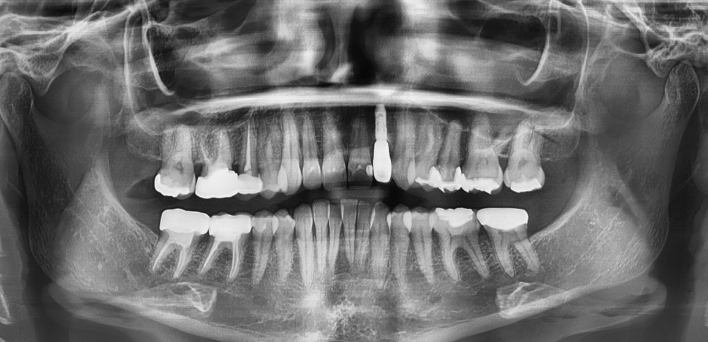

치아가 없어, 음식을 씹지 못했던 환자분

더서울이 당신의 저녁을 찾아드립니다

음식의 즐거움을 다시 느끼는,

나에게 꼭 맞는 컴퓨터 분석을 활용한 임플란트

임플란트 케이스

임플란트 Before & After

The seoul dental clinic

※ 더서울치과의원은 의료법을 준수하며 위 케이스는 실제 환자의 동의를 얻은 사례로 치료 전, 후가 동일한 환경에서 촬영되었습니다.

환자 케이스에 따라 부작용이 발생할 수 있습니다. 이 부분은 의료진의 충분한 상담과 체크를 통해 예방하고 줄일 수 있습니다.

[임플란트 부작용] 수술 후 관리가 소홀할 경우 출혈, 주위염 등의 부작용이 발생할 수 있어 구강 위생을 철저히 유지하고, 정기적인 검진을 통해 상태를 점검하는 것이 중요합니다.